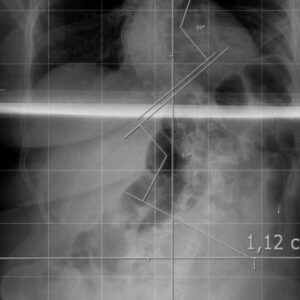

“La escoliosis severa se visualiza a través de radiografías completas de la columna.

Cuando la curvatura supera los 40 grados, evaluamos la intervención quirúrgica”, detalló Reble.

La nueva técnica implica un paso previo crucial: una tomografía del paciente que se carga al sistema de navegación. Este software guía al equipo quirúrgico sobre qué tipo de tornillos utilizar y cómo colocarlos con precisión milimétrica.